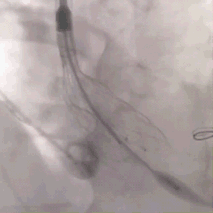

术中影像

VenusA L29号高位释放后发生跳瓣,高位稳定难度大,与FEops预测一致

使用VenusA-Plus回收功能,再次释放高位释放,释放成功